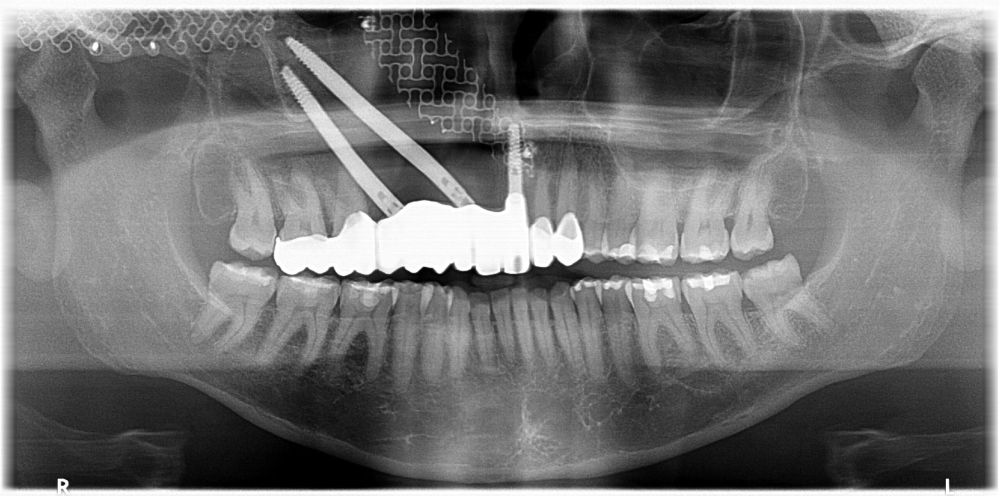

Bajo anestesia general, se realizó la resección quirúrgica junto con la fijación de dos placas preformadas y colocación simultánea de dos implantes cigomáticos y un implante endoóseo en posición del 2.1 (Figuras 5 y 6). Debido a la presencia de márgenes quirúrgicos comprometidos en el informe anatomopatológico, se indicó la administración de radioterapia adyuvante. Por este motivo, se decidió realizar un puente provisional dentosoportado de 1.7 a 2.3 (Figura 7) para mejorar la situación estética y funcional de la paciente durante todo el proceso y evitar un colapso de los tejidos blandos por la radioterapia. Para ello, se tallaron los molares (1.7, 1.6) e incisivo lateral y canino (2.2, 2.3), y se fabricó un puente fresado en polimetilmetacrilato (PMMA) con refuerzo metálico (Figuras 8 y 9).

Una vez finalizada la radioterapia, la paciente se encontraba libre de enfermedad. Por lo que se procedió a la restauración definitiva implantosoportada. Tras la segunda fase, se colocaron dos pilares transepiteliales Multiunit Ò rectos y un pilar Multunit Ò angulado de 17º (Figura 10).

Finalizado el tratamiento oncológico y confirmada la ausencia de enfermedad activa, se procedió a la segunda fase quirúrgica con la colocación de pilares transepiteliales Multiunit®. La integración de los implantes cigomáticos y del implante endoóseo fue satisfactoria, observándose estabilidad clínica y ausencia de signos de periimplantitis.

Las impresiones analógicas y el posterior flujo digital permitieron una correcta planificación protésica. Las estructuras definitivas, confeccionadas en óxido de zirconio monolítico sobre interfases metálicas de titanio, mostraron una adecuada adaptación pasiva tanto clínica como radiográficamente. La prueba estética permitió ajustes oclusales y funcionales mínimos, optimizando el resultado final.